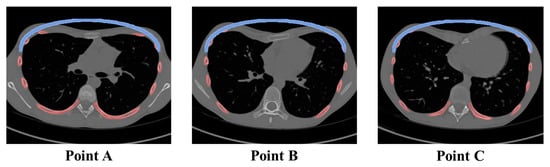

| Type | A (mm): Pre-Op. | A’ (mm): Post-Op. | C (mm): Pre-Op. | C’ (mm): Post-Op. | HI: Pre-Op. | ICI: Post-Op. |

|---|---|---|---|---|---|---|

| Eccentric (Patient No. 2) | 197.2 | 187.34 | 60.4 | 84.4 | 3.26 | 2.22 |

| Unbalanced (Patient No. 3) | 246.0 | 233.7 | 72.6 | 98.6 | 3.39 | 2.37 |